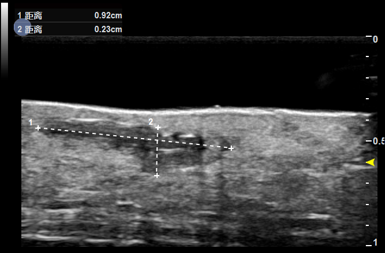

基于全球领先的CMUT半导体超声技术,集成近60项发明专利,珂纳医疗历经数年潜心研制,推出了Paragon XHD便携式彩色多普勒超声系统。该系统显微镜级的成像分辨率,为临床医生观察诊断表皮、真皮、皮下组织及皮肤附件提供了清晰的二维图像。丰富灵敏的彩色多普勒血流成像,满足了对于皮下血流,皮肤肿瘤状态的判定。方便实时的无创操作深受医生和患者青睐,为术前切缘深度测量,术后疗效评估以及医美玻尿酸注射引导等提供了极具价值的诊断信息。